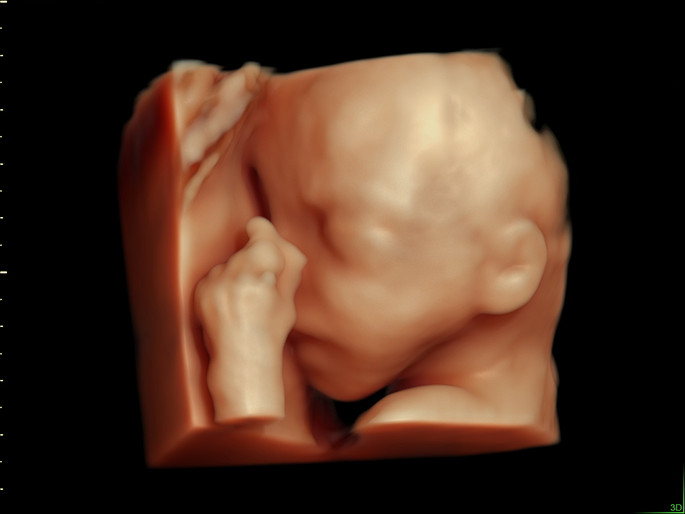

Unter der Pränataldiagnostik (= vorgeburtlicher Ultraschall) werden alle Untersuchungen in der Schwangerschaft zusammengefasst, die die möglichst genaue Beurteilung des ungeborenen Kindes ermöglichen, die frühzeitige Erkennung von Störungen der Entwicklung des ungeborenen Kindes sowie von Schwangerschaftsrisiken der Mutter. Diese Untersuchung wird auch als Fehlbildungs-Ultraschall bezeichnet. Sie wird mit einem hochauflösenden Ultraschallgerät durchgeführt. Damit können bereits in der Frühschwangerschaft viele Organe nicht-invasive beurteilt und untersucht werden.

Die vom Schallkopf ausgesandten Ultraschallwellen werden von den Körperschichten des Kindes reflektiert. Aus den zurückgesandten Schallwellen kann zweidimensionales Ultraschallbild berechnet werden. Dies ermöglicht die Darstellung der kindlichen Organe und die Erkennung möglicher Veränderungen.